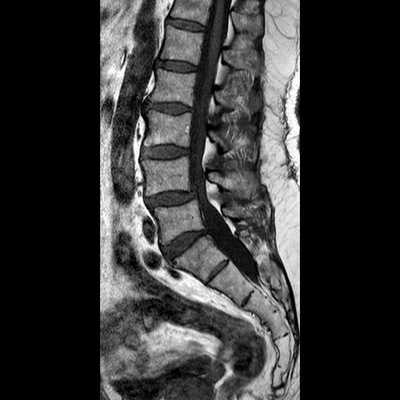

Снимок МРТ поясничного отдела позвоночника в сагиттальной проекции при остеохондрозе

Снимок МРТ пояснично-крестцового отдела позвоночника в сагиттальной проекции (режим STIR)